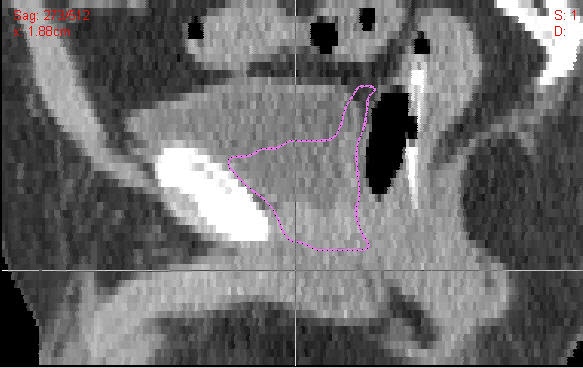

En cuanto a cómo es el tratamiento radioterápico en estos casos, a la hora de definir nuestros volúmenes de tratamiento (CTV: Clinical Target Volumen y PTV: Planning Target Volume) hemos de tener presente que la movilidad del lecho quirúrgico es similar a la de la próstata.

En función de las Tablas de Partin y las Fórmulas de Roach (Riesgo de afectación ganglionar = [2/3 x PSA] + [10 x (GS - 6)]) procederemos a la irradiación pélvica si no se ha realizado una buena linfadenectomía y el riesgo de afectación es elevado (>15%). Por lo demás procederemos a irradiar el lecho quirúrgico (ubicación de la próstata y vesículas seminales) así como el área sospechosa de bordes afectos hasta llegar a una dosis de 66 - 70 Gy a un fraccionamiento diario convencional de 1,8 - 2 Gy/fracción, (a nivel del drenaje linfático, si lo hemos de tratar, daremos una dosis de 45 -50 Gy a ese mismo fraccionamiento).

En caso de que exista una recidiva macroscópica (nódulo visible en lecho de prostatectomía, adenopatía...), si el paciente lo tolera y no desarrolla efectos secundarios importantes se puede llegar a subir la dosis hasta más de 80 Gy. (Además, se pueden valorar rescates con otras técnicas como puede ser la braquiterapia de alta tasa...)